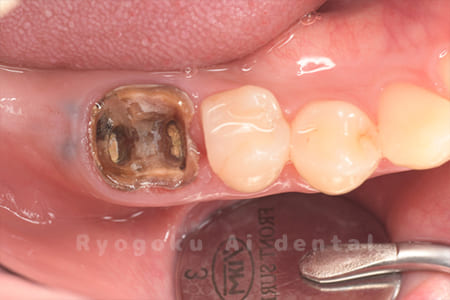

Case14

-

- 抜歯原因

- 重度カリエス

- 治療内容

- クラウンレングスニング治療

- 治療費用

- 44,000円

他院で抜歯と言われた、とのことでご来院された患者さまです。クラウンレングスニングを行い、保存致しました。大変満足して頂けました。

<リスク・副作用>

治療後、痛みや違和感、出血、腫れなどが出る事があります。喫煙者、糖尿病などの方の場合、歯が生着しない場合があります。